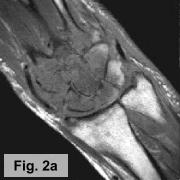

IMAGING FINDINGS:  A triple-phase bone scan was obtained on AIC's dual-head nuclear camera.  Fig. 1a-c show the angiographic (flow) images, blood pool images, and delayed (static) images of the wrists, respectively.  They demonstrate marked increased uptake in the left wrist in all 3 phases of the study.  Fig. 2a-b are selective pre and post-contrast MRI images of the left wrist showing precontrast T1-weighted (Fig. 1a) and postcontrast T1-weighted with Fat SAT (Fig. 1b).  They demonstrate diffuse edema in the marrow of all the carpal bones and proximal metacarpal bones with diffuse enhancement of the marrow and surrounding synovium.  X-rays (not shown) revealed diffuse osteopenia and erosions of the carpal bones.

DIFFERENTIAL DIAGNOSIS:  The bone scan findings are usually seen with osteomyelitis, but diffuse carpal involvement is unusual.  Increased uptake on all 3 phases can also be seen with Reflex Sympathetic Dystrophy (RSD) or an inflammatory process.  The MRI and x-ray findings are more compatible with an inflammatory process, particularly rheumatoid arthritis, with diffuse synovitis and erosions and reactive marrow changes, although this is a late presentation for the patient's age.